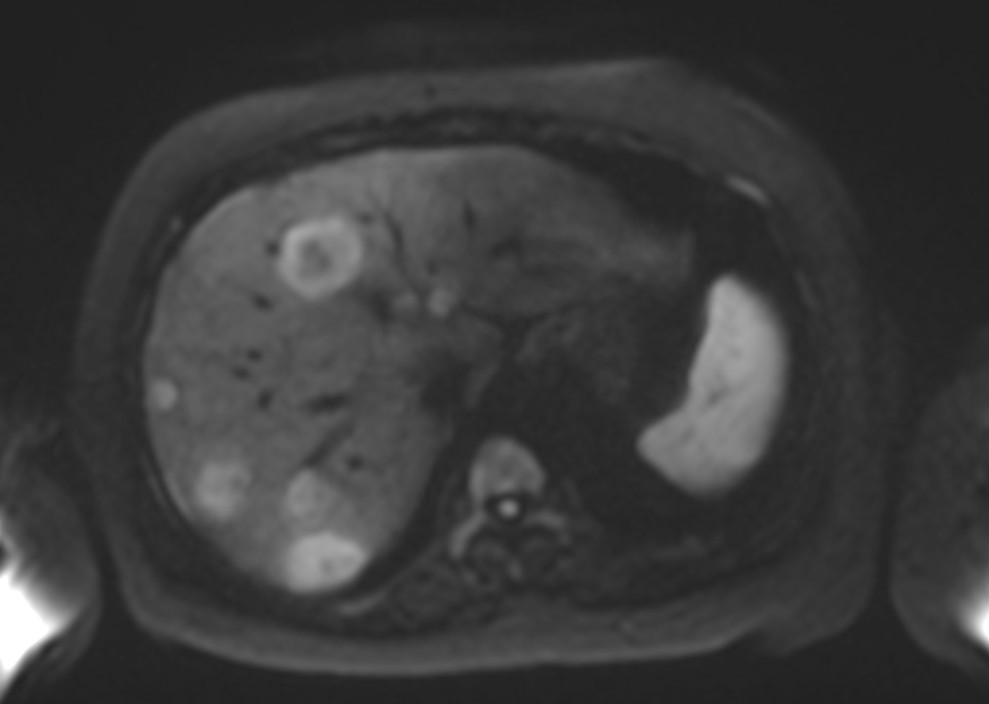

Figure 2b. Axial DWI at b=800 s/mm² demonstrating multiple hyperintense lesions with restricted diffusion corresponding to the PET-positive lesions, with high signal intensity and clear lesion conspicuity.